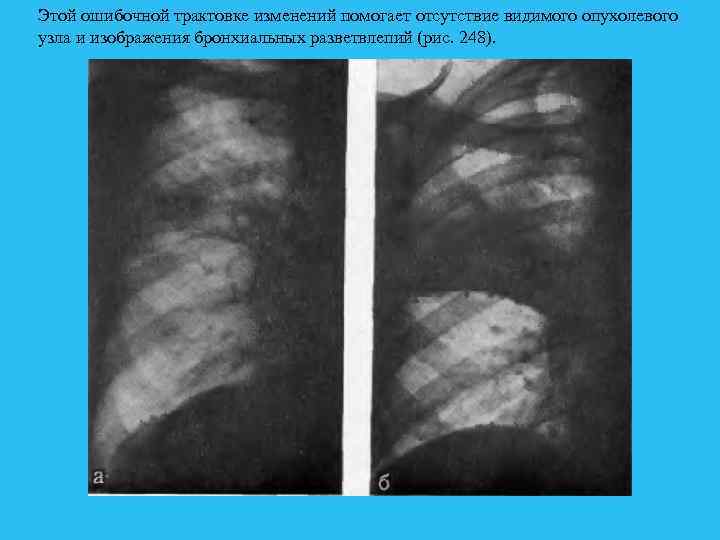

Пневмония и распад. Многократные пневмонии в одном и том же лег ком и особенно в одной и той же доле у лиц старше 30 лет должны вызы вать настороженность. Практика показывает, что под видом сегментарных пневмоний, которые неоднократно фигурируют в анамнезе, часто имеют место относительно ранние стадии развития рака легкого. Нарушение эла стичности стенок бронха, длительное отсутствие вентиляции сегмента или зоны и насасывание жидкости в альвеолы почти всегда способствует раз витию воспалительного процесса в данной анатомической области легкого. В развитии пневмонии играют роль и микроорганизмы, имеющиеся в ды хательных путях, которые находят благоприятную почву в виде богатого белком экссудата в альвеолах. Нередко именно острое начало заболевапия заставляет больного обратиться к врачу, и уже первое рентгенологическое исследование указывает на опухолевый процесс. В данном случае осложнение уже давно развивающегося рака в виде остро возникшей ппевмонии по существу является первым осознанным проявлением заболевания. Развитие воспалительной инфильтрации в недостаточно дренируемом участке бронха приводит к возникновению неоднородного затемнения. Эта неоднородность связана с сохранепием воздушности в отдельных альвеолах и образованием плотных фокусов воспалительного уплотнения. Именно наличием воспалительного процесса объясняется тот факт, что при полной обтурации бронха можно видеть нормальные размеры сегмента или зоны, а в некоторых случаях даже отметить некоторое увеличение их объема. Отсутствие спадения пораженного отдела легкого является наиболее частой причиной ошибочной интерпретации характера пневмонии, являющейся вторичной и обусловленной развитием рака.

Этой ошибочной трактовке изменений помогает отсутствие видимого опухолевого узла и изображения бронхиальных разветвлепий (рис. 248).

Если при томографическом исследовании не удается получить отчетливого изображения нужного бронха, больного следует исследовать повторно, через короткий срок после курса антибактериальной терапии. Уменьшение плотности тени из за рассасывания воспалительных фокусов дает возмож ность получить изображение бронхов при томографическом исследовании. Если и при этом исследовании получить отображение бронхов пе удается, нельзя отпускать больного без бропхологического исследования, включаю щего бронхоскопию с зондированием бронхов (рис. 249). Очевидно, что всех больных с пневмонией детально бронхологически исследовать невозможно, однако с учетом возраста, предшествующих легочных заболеваний и длительности течения должен быть проведен правильный отбор с тенденцией более широкого использования современных ме тодов бропхологического исследования. Если бронхологическое исследо ание дает отрицательные результаты, то при сомнительной общей рент ренологической картине следует произвести бронхоскопию. Часто приходится убеждаться в том, что своевременно проведенная бронхоскопия избавляет от ошибки даже в тех случаях, когда материалы, взятые для гистологического изучения, не указывают па наличие рака легкого. По мере прогрессирования воспалительного процесса при раке соответствующего сегмента (пли доли) может наступить гнойное расплавление